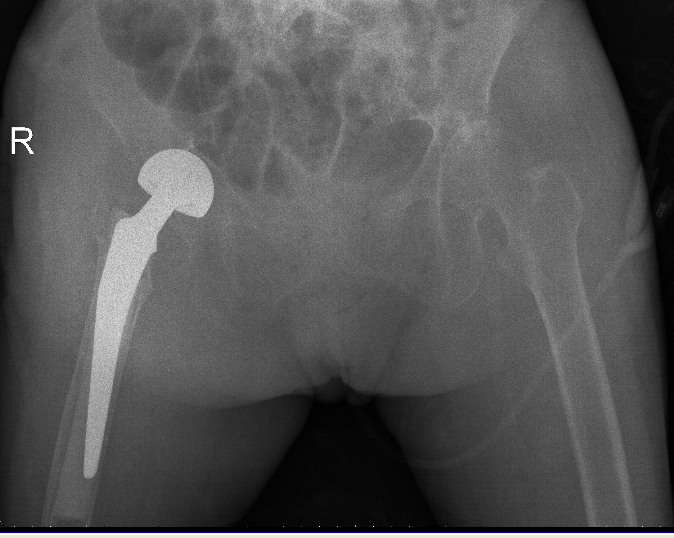

吳志斌主任通過CT+三維重建先行拟定詳細手術方案,提前做了精心準備。根據患者的年齡特征,爲其選擇最佳的半髋置換方案,并采用雙動人工股骨頭,提高活動範圍,減少髋臼磨損。

10月20日,老人家被送進了手術室行左側人工股骨頭置換術。吳主任根據方案按部就班地實施手術,娴熟地完成每一個手術步驟,精心地把控每一個細節,确保髋部良好的活動性和穩定性,以及雙下肢等長。整個手術過程非常流暢、一氣呵成。術中患者各項生命體征平穩,術後平安返回病房。

△右側(R)是賴婆婆3年前跌斷股骨術後,左側是本次手術術後。